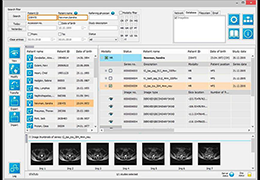

Load DICOM data directly from PACS, CD/DVD, USB, and local computer.

Upload DICOM data to your PACS directly from referral patient CD/DVD and local computer.

Easy to use patient search to locate patient data on your PACS.